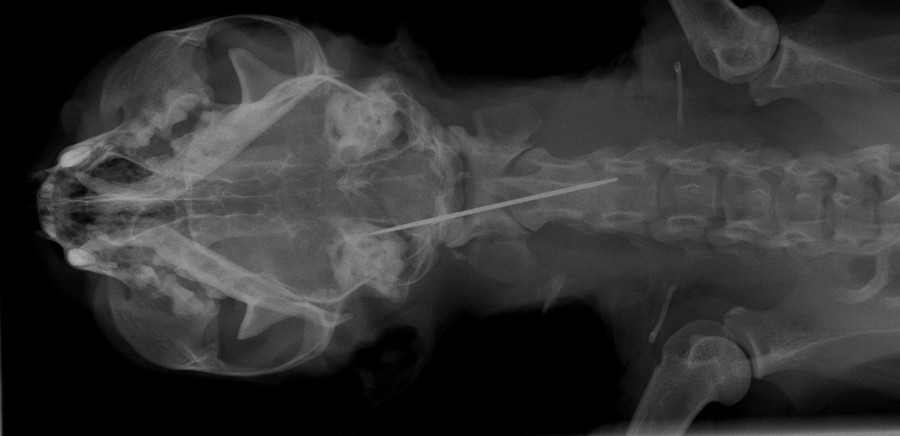

Sind unsere vierbeinigen Familienmitglieder krank, sollen auch sie optimal behandelt werden. Von Ultraschall bis Magnetresonanztomographie, von Chemotherapie über Laserchirurgie bis zu künstlichen Gelenken – vieles, was die Humanmedizin zu bieten hat, wird auch in der Kleintiermedizin angewendet. Die Klinik für Kleintiere gewährt im Rahmen einer "Nacht der offenen Tür" Einblicke in die moderne Kleintiermedizin in Leipzig. Auf dem Rundgang laden viele Mitmach-Aktionen ein, selbst tätig zu werden.